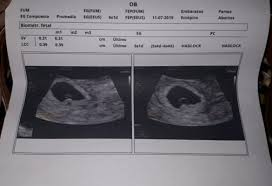

Recordemos que en esta semana el embrión tiene cuatro semanas de edad ya que habitualmente al contabilizar las semanas de embarazo se empieza desde la. Aproximadamente 6 semanas más o menos en el embarazo los latidos del corazón del feto se pueden detectar a través de un ultrasonido que sin embargo puede variar mucho en situaciones reales.

NO SE ESCUCHA EL LATIDO DE MI BEBE. De ahí la importancia de la suplementación de ácido fólico en el embarazo. Fue la mejor noticia que nos dieron a mi y a mi novio y estamos ilusionados pero ahora estamos y especialmente yo estoy muy tristeee porque estoy de 8 semanas y el latido del corazon de mi bebe no se escucha. Cuando no es posible ver el embrión yo escuchar sus latidos cardiacos la mujer tendrá que repetirse la ecografía de ultrasonido pasadas una o dos semanas para descartar la posibilidad de que se trate de un embarazo anembrionado. El latido del feto es uno de los indicadores del crecimiento la salud y el desarrollo del bebé. Aproximadamente 6 semanas más o menos en el embarazo los latidos del corazón del feto se pueden detectar a través de un ultrasonido que sin embargo puede variar mucho en situaciones reales. El cerebro del futuro bebé se va a desarrollar rápidamente desde este momento y su corazón ya late de manera regular pudiéndose observar su bombeo mediante una ecografía. El embrión en la semana 6 de embarazo. La actividad cardiaca no se inicia antes de los 28 días de embarazo porque durante las cuatro primeras semanas tras la fecundación tu futuro bebé tiene muchas cosas que hacer.

No escuchar el latido del feto a las 6 semanas es normal y no hay razón para preocuparse. Aproximadamente 6 semanas más o menos en el embarazo los latidos del corazón del feto se pueden detectar a través de un ultrasonido que sin embargo puede variar mucho en situaciones reales. El corazón de un feto late muy rápido no debes asustarte cuando te realizen la ecografía y escuches un latido a 150 pulsaciones porque es normal. La actividad cardiaca no se inicia antes de los 28 días de embarazo porque durante las cuatro primeras semanas tras la fecundación tu futuro bebé tiene muchas cosas que hacer. Cuando no es posible ver el embrión yo escuchar sus latidos cardiacos la mujer tendrá que repetirse la ecografía de ultrasonido pasadas una o dos semanas para descartar la posibilidad de que se trate de un embarazo anembrionado. Los médicos generalmente no recomiendan un ultrasonido a las 6 semanas ya que generalmente no muestra nada o muy poca imagen del feto incluso para un embarazo. Fue la mejor noticia que nos dieron a mi y a mi novio y estamos ilusionados pero ahora estamos y especialmente yo estoy muy tristeee porque estoy de 8 semanas y el latido del corazon de mi bebe no se escucha.